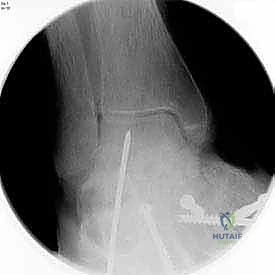

3. التصوير الشعاعي (X-rays): صور أشعة سينية أثناء الوقوف (Weight-bearing) لتقييم زوايا العظام ودرجة انهيار المفاصل.

تستغرق هذه الجراحة الدقيقة عادة من ساعتين إلى ثلاث ساعات، وتتم تحت التخدير النصفي أو العام. إليك الخطوات الجراحية كما يجريها الأستاذ الدكتور محمد هطيف باحترافية عالية:

1. الشقوق الجراحية (Incision & Approach)

يتم إجراء شقين جراحيين للوصول إلى المفاصل الثلاثة:

* شق خارجي (Lateral Incision): للوصول إلى المفصل تحت الكاحل والمفصل العقبي المكعبي.

* شق داخلي (Medial Incision): للوصول إلى المفصل الكاحلي الزورقي.

يحرص الدكتور هطيف على حماية الأعصاب والأوعية الدموية الحساسة المحيطة بالمنطقة.

5. التثبيت الداخلي (Internal Fixation)

بعد التأكد من الوضعية المثالية للعظام، يتم تثبيتها بقوة باستخدام مسامير معدنية مجوفة من التيتانيوم (Cannulated Screws) أو شرائح معدنية خاصة. يتم إدخال المسامير تحت توجيه الأشعة السينية المباشرة (Fluoroscopy) داخل غرفة العمليات لضمان الدقة المتناهية. هذه المسامير تضغط العظام معاً وتمنع أي حركة حتى يحدث الالتئام التام.